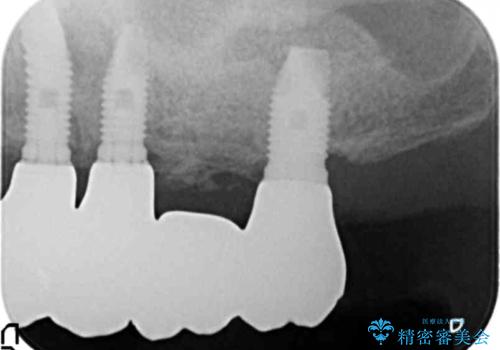

禁煙指導と歯周病治療後、左上臼歯部のソケットリフト(上顎洞底挙上術)及びインプラント治療(左上457埋入)を行いました。

インプラントが長持ちするように、角化歯肉(歯ブラシが当たっても痛くない固くしっかりした歯茎)の移植(遊離歯肉移植術:FGG)も行いました。

- ¥1,617,000 (ソケットリフト、遊離歯肉移植術、インプラント×3本、アバットメント×3本、仮歯×4本、クラウン×4本) ※税込費用は治療当時の料金となります

インプラントの種類:スプラインツイスト(HAコーティング)

固定様式:スクリュー固定

クラウンの種類:ベレッツァクラウン